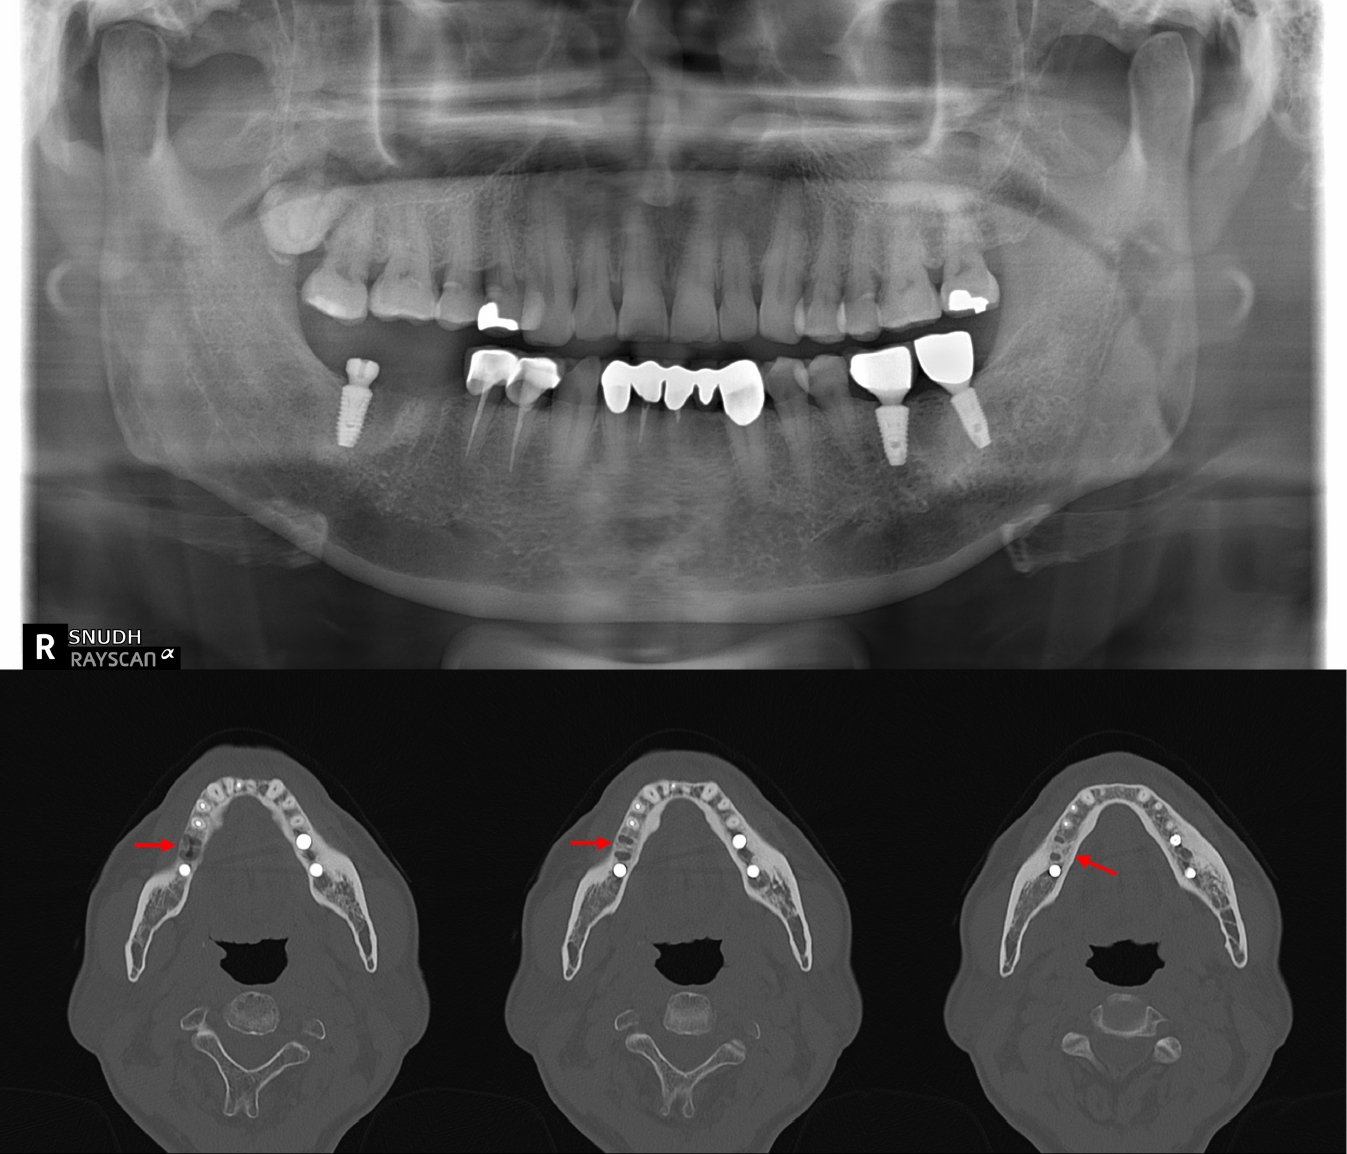

Initial panoramic view and non-contrast computed tomography (CT) of the mandible showed thickening of the lamina dura and irregular residual alveolar crest at the #46 extraction site (Fig. 1). Based on the clinical presentation and radiologic findings, the patient was diagnosed with incipient osteomyelitis of the right mandibular body, and oral antibiotic therapy was initiated.

Fig. 1.

Initial panoramic and computed tomography (CT) imaging findings of the mandible. Panoramic radiograph shows the extraction socket at the #46 site. Non-contrast axial CT image reveals thickening of the lamina dura and irregular residual alveolar crest at the right mandibular body (arrows), consistent with early-stage osteomyelitis.

Fig. 1. Initial panoramic and computed tomography (CT) imaging findings of the mandible. Panoramic radiograph shows the extraction socket at the #46 site. Non-contrast axial CT image reveals thickening of the lamina dura and irregular residual alveolar crest at the right mandibular body (arrows), consistent with early-stage osteomyelitis.